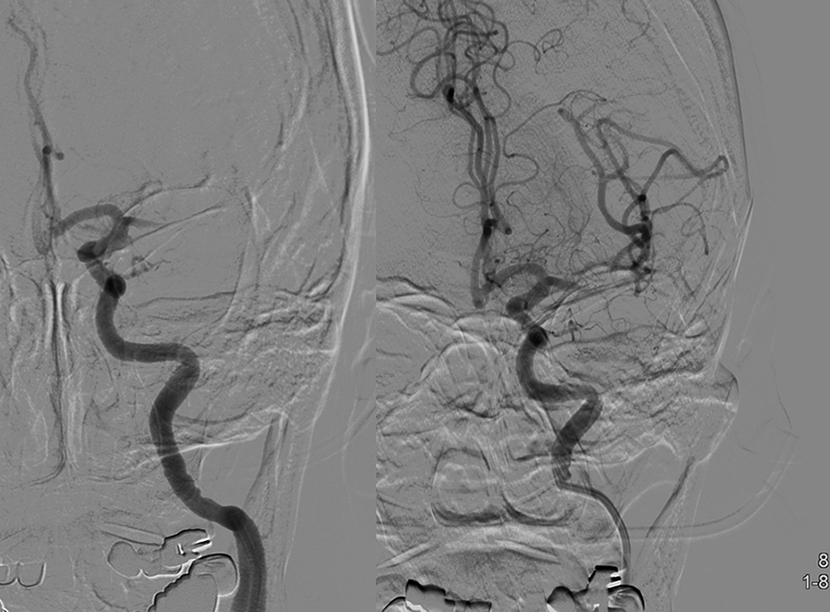

뇌혈관조영술로 동맥류에 대해 정밀검사

혈관내 코일색전술을 통해 개두술 없이 동맥류를 치료함